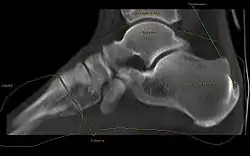

Die Ferse (regional auch Hacke(n)[1]) ist bei Säugetieren die Vorwölbung am hinteren Teil des Fußes. Ihre Kontur erhält sie durch das Fersenbein (von lateinisch Calcaneus) und das darüberliegende Fettgewebe und die Haut. Die Ferse ist Ansatz für die Achillessehne, auf beiden Seiten von ihr fällt die Haut etwas ein.

Beim Fersensporn zeigt sich im Röntgenbild eine knöcherne Ausziehung am Ansatz der Achillessehne am Fersenbein oder am Ursprung der Plantaraponeurose (Sehnenplatte der Fußsohle).